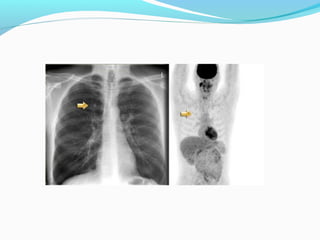

FDG UPTAKE

STAGE ??